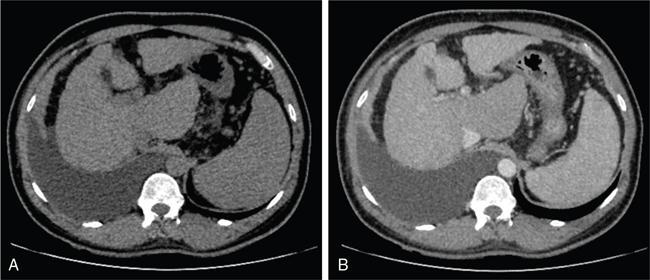

Ritu K. Kashikar, Shrinivas B. Desai Knowledge regarding normal dimensions of organs is important as visceromegaly is the first and often only abnormality in a variety of disorders. The radiologist should also be aware of normal diameters of vessels and ducts because an increase in size is usually a pointer to pathology in the organ. This chapter is a lucid review of normal sizes of organs, vessels, duct and also focuses on which section and location should size be measured to avoid interobserver variation. The liver is the largest organ in the abdomen. Hepatomegaly is a common condition and often the first clinical and imaging feature of various disorders. It is hence imperative for the radiologist to know the normal size and the section on which measurements should be taken. USG is commonly used to measure liver size. The longitudinal view is commonly used to measure liver size. The liver is considered normal in size if on longitudinal scan through the midhepatic line the liver measures 13 cm or less. This is true in approximately 93% individuals Measurement more than 15.5 cm suggests hepatomegaly in 75% cases (Figs. 9.3.1 and 9.3.2) (Table 9.3.1). Hepatomegaly is also suggested by an inferior angle of more than 45 degrees in the left lobe and more than 90 degrees in the right lobe. The normal liver measures approximately 6.5 cm first 3 months of age and reaches a size of 12.5 cm by 10–12 years of age. Liver size can be measured on unenhanced or enhanced CT. On CT the liver measures 10–12.5 cm in the midclavicular line on an average. A liver measuring more than 15.5–16 cm in the midclavicular line is considered enlarged. The midclavicular line measurement is done in coronal plane (Fig. 9.3.3). Another important measurement is the size of caudate lobe. The caudate to right lobe ratio (C/RL) is a measurement used to diagnose caudate lobe hypertrophy and right lobe atrophy which is important in the diagnosis of cirrhosis. The axial section immediately below main portal vein bifurcation is used for measurements. The following lines are drawn on the liver (Fig. 9.3.4). C/RL: In an adult patient of average weight (60 kg), the estimated liver volumes can range from 1024–1302 cm3 (Fig. 9.3.6). USG and Doppler provide important information regarding patency of artery in postoperative/transplant setting. Normal hepatic artery waveform is pulsatile and of low resistance. The normal resistive index measures 0.7. High or low resistivity index (RI) indicated pathology. The measurements of the hepatic arteries bare importance in transplant imaging. The diameter and length of the arteries are best measured on CT angiogram images. Arteries smaller in calibre than 2 mm may be difficult to anatomize. Replaced RHA is often longer in length than standard arteries. The normal diameters of the hepatic arteries are mentioned in Table 9.3.2 (Figs. 9.3.7–9.3.9). The portal venous system is valveless and hence its diameter is influenced by respiratory variations. The portal venous diameter is greatest during inspiration and hence all measurement should be made in this phase (Table 9.3.3). The diameter of portal vein has importance in diagnosing portal hypertension and USG is often used for this purpose. USG also provides other important parameters like flow velocity and volume flow which are relevant in the setting of portal hypertension. The normal portal venous velocity measures 15–18 cm/sec.(Fig. 9.3.10)

Measurement of caudate lobe

Interpretation